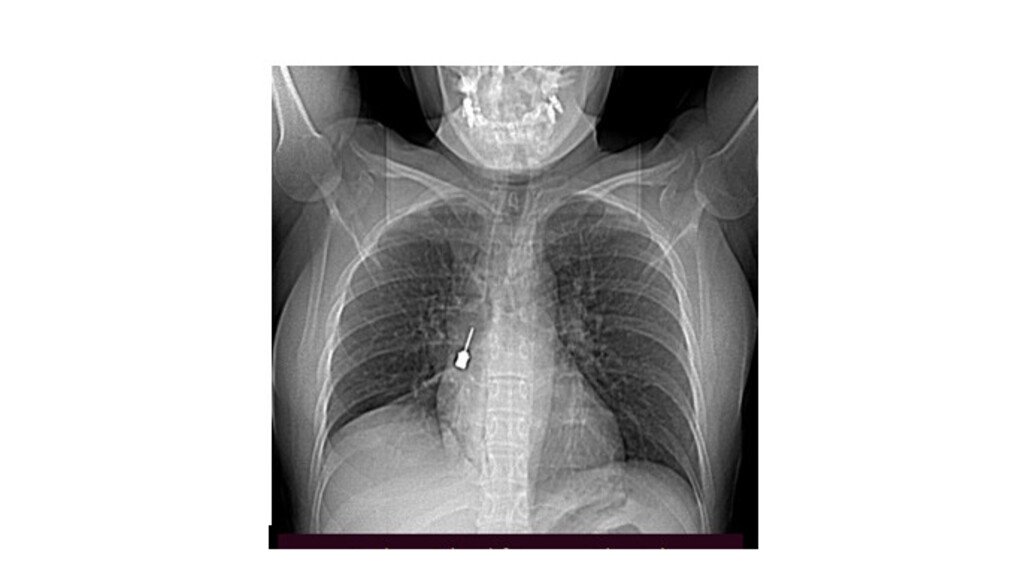

La paziente è giunta al Pronto Soccorso del G.O.M. esibendo un esame di diagnostica per immagini (Tomografia Computerizzata) eseguito a causa di una tosse persistente e di un forte dolore a livello toracico. La TC mostrava la presenza di un corpo estraneo metallico pericolosamente incastrato nel bronco lobare inferiore del polmone destro e un concomitante pneumomediastino, ossia la presenza di aria nello spazio compreso fra i due polmoni.